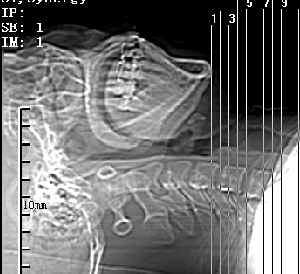

标题: CT28317:病人近几天无意间发现颈部肿块。 [打印本页]

标题: CT28317:病人近几天无意间发现颈部肿块。

甲状腺左叶局限性结节性甲状腺肿可能。建议增强扫描。

病变边界清楚,周围间隙清晰,甲状腺左叶(甲状旁腺?)肿大,右叶甲状腺腺瘤。

病变边界清楚,周围间隙清晰,左叶甲状腺肿大,右叶甲状腺小腺瘤。